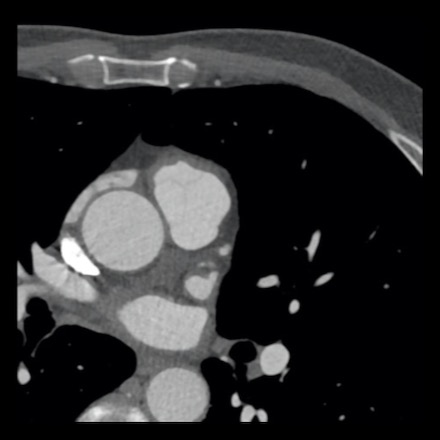

Same patient. First, study the CTA image.

The coronal image shows a central low-attenuation area around the lumen

of the LAD.

This low-attenuation area is surrounded by a higher attenuation

area.

This finding is the earlier discussed napkin-ring sign, which is a high-risk

plaque feature.

This patient classifies as CAD-RADS 4A/P1/HRP.